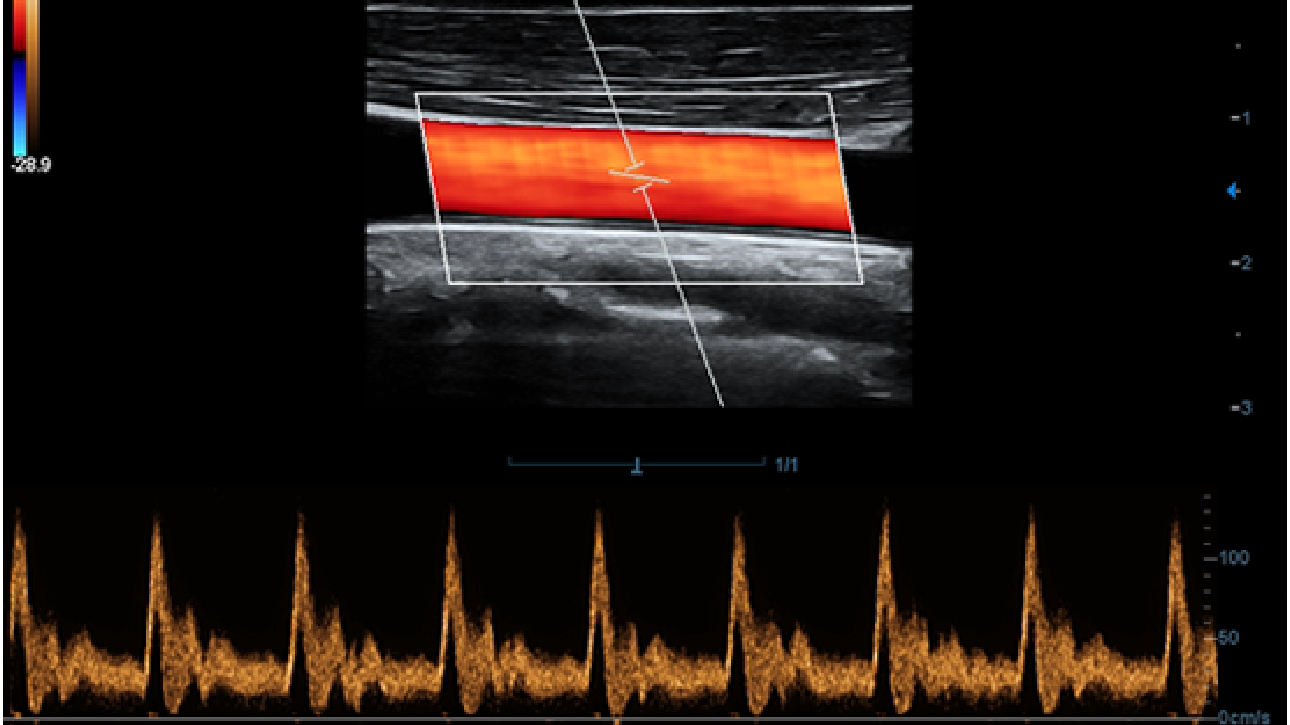

X-Insight is een inzichtelijke oplossing om meer visie te krijgen.

De gloednieuwe oplossing van Mindray is het geslaagde product dat is voortgekomen uit voortdurende klantinzichten in klinische behoeften in combinatie met steeds evoluerende, geavanceerde ultrasoundtechnologie?n. Vol energie en gebrand op toekomstgerichte inzichten en eindeloze mogelijkheden: dankzij de verhoogde schaalbaarheid wordt de oplossing continu verbeterd.

Als allround partner zet DC-60 Exp met X-Insight zich in om een allesomvattende oplossing te zoeken waarmee u alle aspecten van uw dagelijkse klinische activiteiten gemakkelijk en trefzeker kunt beheren.

De DC-60 Exp met X-Insight is ontworpen op basis van diepgaand inzicht in klantbehoeften om hoge effici?ntie met nauwkeurige beeldverwerking te leveren, dankzij eXacte helderheid, eXceptionele intelligentie en eXcellente ervaring.